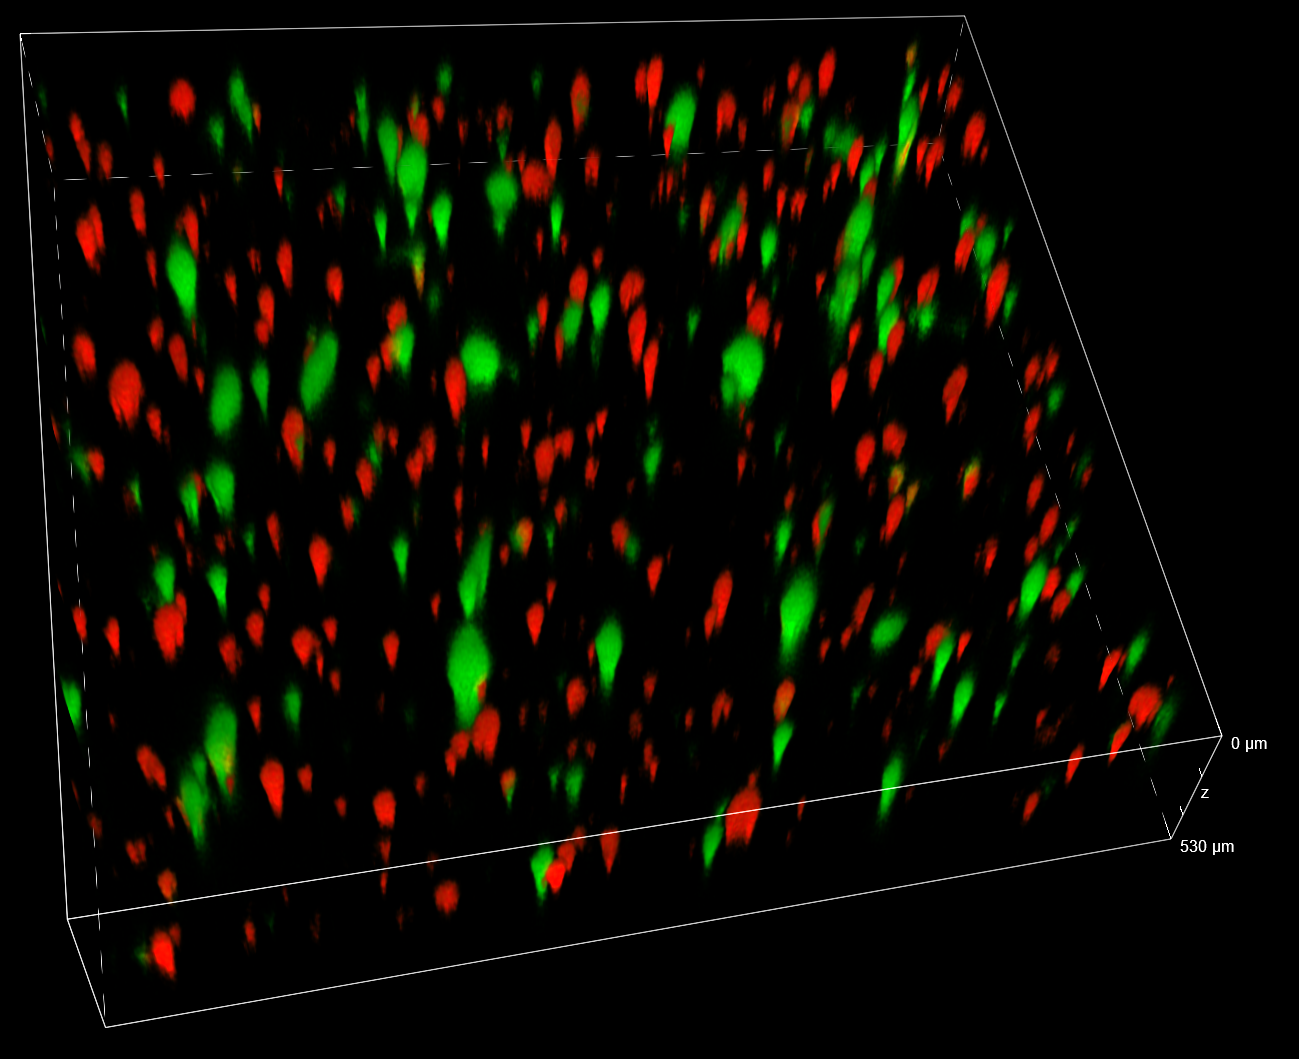

Three VITVO areas were monitored along the Z axis and over time in order to record movies. A representative entire movie of one of three areas enables to appreciate the intense activity of AD-MSCs TRAIL (green) moving towards A673 tumour cells (red), which showed a dramatic change in their cell morphology (Figure 3).

Figure 3. Representative movie recorded in one of the three VITVO areas with spinning disk. The deconvolved Z-maximum intensity projection of each time frame is shown.

To confirm that the apoptotic effects observed were not due to laser exposure during the video-recording, we compared the laser exposed area (FOV (i)) with a not-exposed area inside VITVO (FOV (ii)). Z-stack acquisitions performed by using the same settings used during the time lapse, allow to confirm that both area coverage and cell density were comparable between FOV (i) and (ii), as shown in the 3D render visualization (Figure 6).

Figure 6. 3D views collected in VITVO at 96 h post-treatment by spinning disk acquisitions. FOV (i) of a VITVO exposed area during time lapse movie and FOV (ii) of a not-exposed area (4x objective magnification).